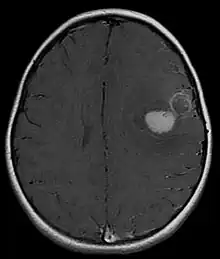

Primitive neuroectodermal tumor of the central nervous system in a 5-year-old

Magnetic resonance image of PNET

Most children that develop primitive neuroectodermal tumors are diagnosed early in life, usually at around 3–6.8 years of age.[2] Symptoms patients present at time of diagnosis include irritable mood, visual difficulties, lethargy, and ataxia.[2] The circumference of the patient's head might also become enlarged and they might be subject to seizures, especially if they have less than one year of life.[2]

Several analysis can be used to determine the presence of the disease. Physical examinations showing papilledema, visual field defects, cranial nerves palsy, dysphasia, and focal neurological deficits are evidences for possible tumor.[2] PNETs can also be spotted through computed tomography (CT) and magnetic resonance imaging (MRI).[2] In images produced by MRIs, an irregular augmentation among a solid mass will indicated the presence of tumor.[3] However, the results of MRIs are usually ambiguous in defining the presence for this specific tumor.[2] In CT scans, the presence of PNETs will be indicated by an elevated density and an increase in volume of the brain.[2] The CT scan can also show calcification,[3] which is present in 41-44% of PNET cases.[2] Since the tumor can be replicated in other parts of the nervous system through the cerebrospinal fluid (CSF), a CSF analysis can also be conducted.[2] A spinal MRI is a fourth type of analysis that is useful in investigating the level of tumor propagation to the spinal cord.[2]